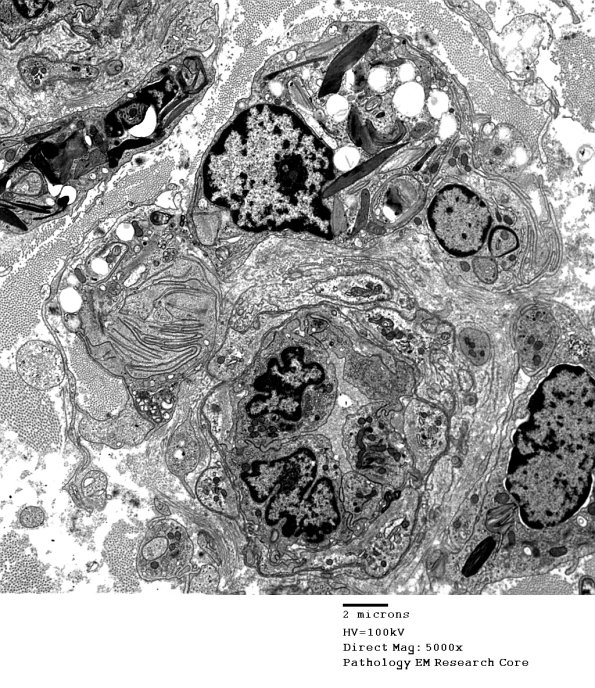

Washington University Experience | PERIPHERAL NEUROPATHY | 4 AXONAL DEGENERATION | 4 Macrophages | 4M Axonal Degeneration (Case 4) 051 - Copy

Additional example of pi granules in a macrophage lining up along this vessel.